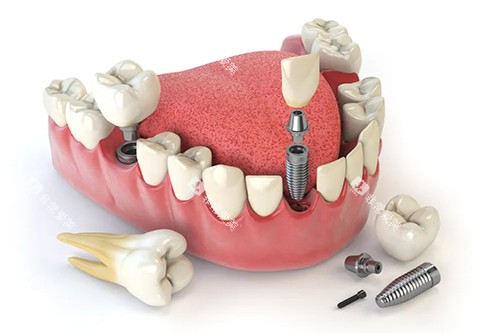

从普通的牙齿清洁、补牙,到复杂的牙齿矫正、种植牙手术,这里都配备了相应的特色设备和经验充足的医生团队。

例如,他们拥有靠前的口腔全景CT机,能够清晰地拍摄口腔内部的三维图像,为医生比较准诊断病情提供有力依据。